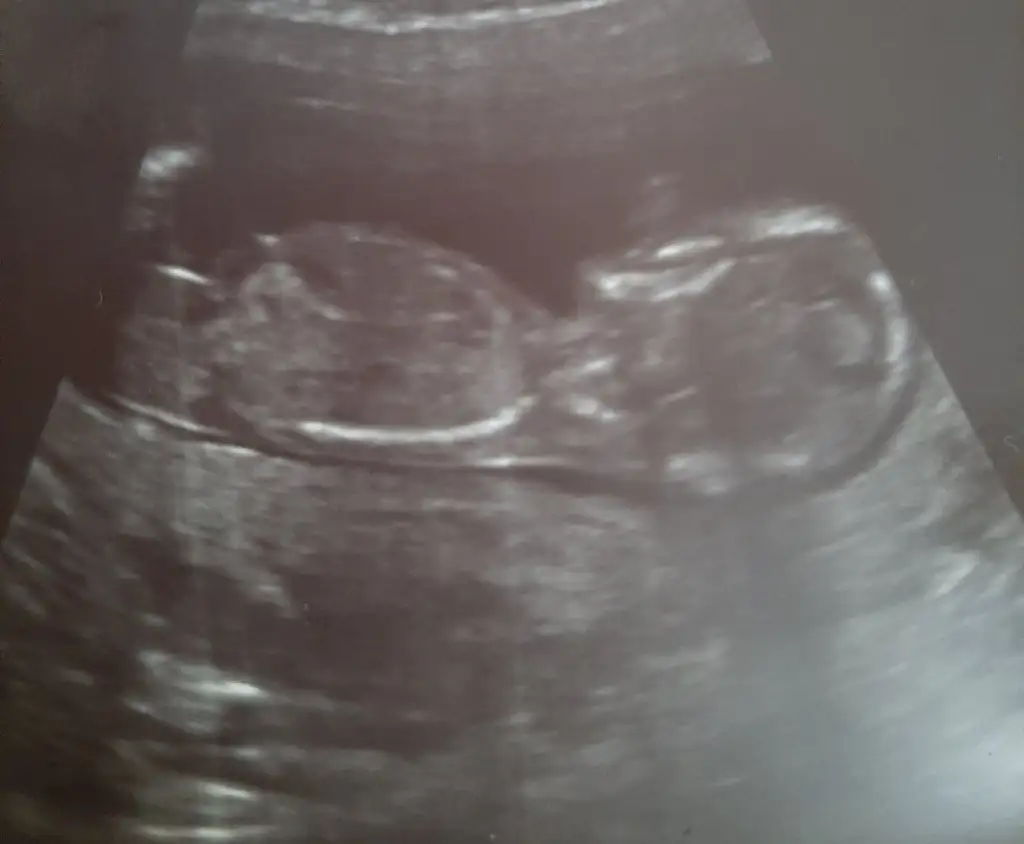

Kız13+0 haftalık olduk bize de lütfen yorum yaparmısınız

Erkek gibi sanki13+0 haftalık olduk bize de lütfen yorum yaparmısınız

Erkek gibi görünen yeri bana gösterebilirmisin canım zahmet olmazsa. Ben o kadar baktım anlamadım açıkçasıErkek gibi sanki

Pipi orda mı bende başka yere bakıyordum. Ben buraya bakıyordum valla

O kordon olabilir çizdim diklik var gibiPipi orda mı bende başka yere bakıyordum. Ben buraya bakıyordum valla

Yani öyle görünüyor emin olamadım erkek gibi sanki diyorumSağol Canim Allah razi olsun